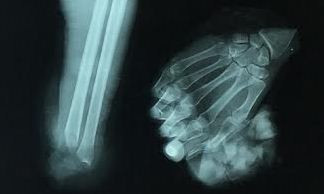

Phim X-quang bàn tay trái bị đứt lìa trước khi được nối của ông T. Ảnh do bệnh viện cung cấp.

TPO - Ngày 5/8, Bệnh viện Chấn thương chỉnh hình TPHCM cho biết đã phẫu thuật thành công một tai nạn lao động nghiêm trọng khiến người công nhân bị đứt lìa cổ tay trái.

Theo bác sĩ Võ Hòa Khánh - Phó trưởng phòng quản lý chất lượng, bệnh nhân là anh Tống Xuân T. (37 tuổi, ngụ TPHCM), nhập viện cấp cứu trong tình trạng mất máu, phần cổ tay bị đứt lìa được giữ lạnh trong thùng đá đúng cách. Ê kíp của bác sĩ Khánh đã lập tức tiến hành vi phẫu cắt lọc da, gân cơ, thần kinh, mạch máu bị dập nát nhằm loại bỏ nguy cơ nhiễm trùng.

Ca mổ hơn 4 tiếng đồng hồ kết hợp xương, nối động mạch, tĩnh mạch, dây thần kinh, gân gấp, gân duỗi dưới kính hiển vi, để mọi giá cứu bàn tay và các ngón tay của bệnh nhân. Do bị mất máu nhiều nên ông T. được truyền máu, truyền dịch ngay trong lúc mổ. Hai tuần sau phẫu thuật, bàn tay và các ngón tay bệnh nhân đã “sống” hoàn toàn, không có dấu hiệu nhiễm trùng.